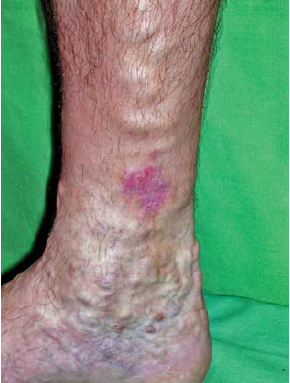

2. A corona phlebectatica (6. ábra) hozzáadása a C4 osztályhoz és ezzel a 3. alcsoport létrehozása (C4a, C4b, C4c). A 2008-as terminológia szerint a corona phlebectatica számos, kis, intradermális, legyező elrendeződésű véna képe, a boka és a lábfej mediális, vagy laterális oldalán. Szinonimái: malleolaris, vagy boka "flare" (kiöblösödések). Régebben ezt a bőrelváltozást a teleangiectasiák (7. ábra) közé sorolták.

Indokolt volt az újabb alosztály megjelölése, hiszen a teleangiectasiáktól elhelyezkedésében, a reticularis vénáktól (8. ábra) méretében különbözik. Újabb kutatások alapján, ezeken kívül a corona phlebectatica kék teleangiectásiái az előrehaladó vénás betegség korai jele. Bihari a corona phlebectatica paraplantaris mikrocirkulációját vizsgálva megállapította, hogy a gyorsult nyugalmi áramlás és a nagy amplitúdó értékek arra utalnak, hogy az elváltozást AV shunt kinyílás okozza (13) (4. táblázat).